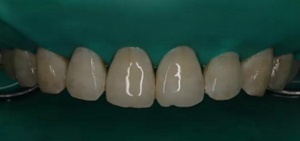

1,術前照片,全口氟斑牙,前牙表面釉質(zhì)白堊色+黃色斑點+凹坑缺損。

術前正面?zhèn)让嬲掌?/span>

(下圖是上頜打磨后與下頜術前未研磨對比,區(qū)分打磨效果和目的)

(下圖是拋光完成)

治療完成的上頜牙齒和未治療的下頜牙齒形成明顯對比。